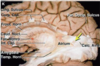

Key gyri on the lateral surface of the frontal lobe

Superior frontal gyrus

Middle frontal gyrus

Inferior frontal gyrus (pars triangularis, pars orbitalis, pars opercularis)

Precentral gyrus

Key sulci on lateral surface of frontal lobe

Superior frontal sulcus

Inferior frontal sulcus

Pre-central sulcus